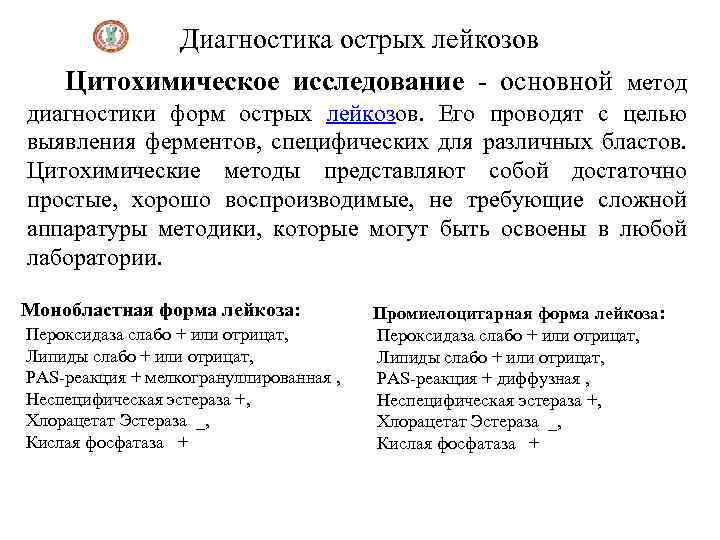

Диагностика острых лейкозов Цитохимическое исследование - основной метод диагностики форм острых лейкозов. Его проводят с целью выявления ферментов, специфических для различных бластов. Цитохимические методы представляют собой достаточно простые, хорошо воспроизводимые, не требующие сложной аппаратуры методики, которые могут быть освоены в любой лаборатории. Монобластная форма лейкоза: Пероксидаза слабо + или отрицат, Липиды слабо + или отрицат, PAS-реакция + мелкогрануллированная , Неспецифическая эстераза +, Хлорацетат Эстераза _, Кислая фосфатаза + Промиелоцитарная форма лейкоза: Пероксидаза слабо + или отрицат, Липиды слабо + или отрицат, PAS-реакция + диффузная , Неспецифическая эстераза +, Хлорацетат Эстераза _, Кислая фосфатаза +